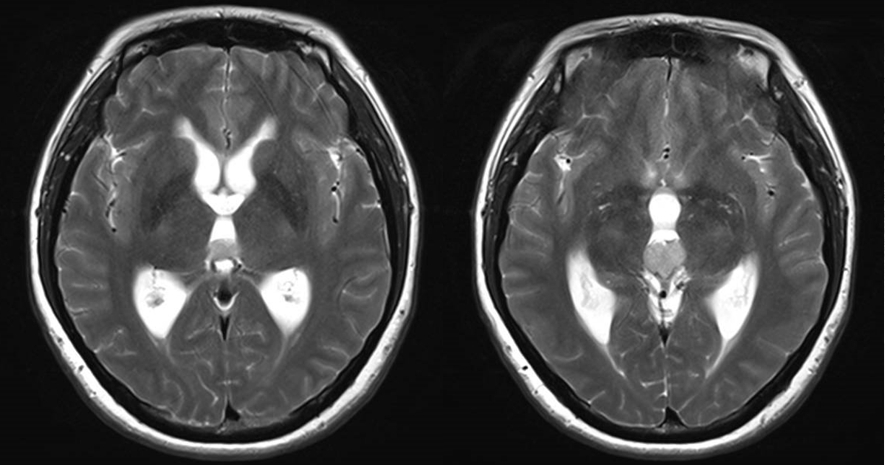

中年女性,因“头痛伴记忆力减退1月” 入院;

查体:神志清醒,反应迟钝,精神差,高级认知功能差,双下肢肌力IV级;

诊断:三脑室占位,梗阻性脑积水。

诊治过程:结合患者临床表现及影像学表现,初步诊断考虑为三脑室后部胶质瘤合并梗阻性脑积水可能性大,术前制定的手术方案为经胼胝体穹隆间入路三脑室后部肿瘤切除术+脑室镜辅助下三脑室底造瘘术,该手术方式既可切除肿瘤获取病理,同时可行三脑室底造瘘解决脑积水症状。术中采用冠状缝前额部弧形切口,术中沿纵裂牵开双侧大脑半球,探及胼胝体,沿中线切开胼胝体,分离双侧透明隔,暴露双侧穹隆,严格沿中线分离双侧穹隆,保护两侧穹隆的完整,避免引起术后的记忆力障碍,牵拉开双侧穹隆,进入中间帆,显露并分离双侧大脑内静脉继续向下,经脉络膜隔进入三脑室,完全显露肿瘤组织,肿瘤组织呈灰红色,血供极其丰富,与中脑黏连紧密,仔细分离,分块全切肿瘤,双侧大脑内静脉及中脑保护良好,中脑导水管通畅。肿瘤完全切除后,考虑到术后局部粘连、肿瘤复发等因素可能导致脑积水不缓解,置入脑室镜向前方探查,小心切开中间块,在双侧乳头体与漏斗隐窝之间,行三脑室底部造瘘并打开Liliequist膜及基底动脉旁蛛网膜,确认漏口通畅且与脚间池相通。患者术后恢复过程平稳,颅脑MRI提示肿瘤切除满意,脑积水缓解。术后病理结果示:中枢神经细胞瘤(2级)。术后予以放疗GTV 5400cGy、PTV 5040cGy,28f。现术后已3年,复查未见肿瘤复发,脑积水已完全缓解。